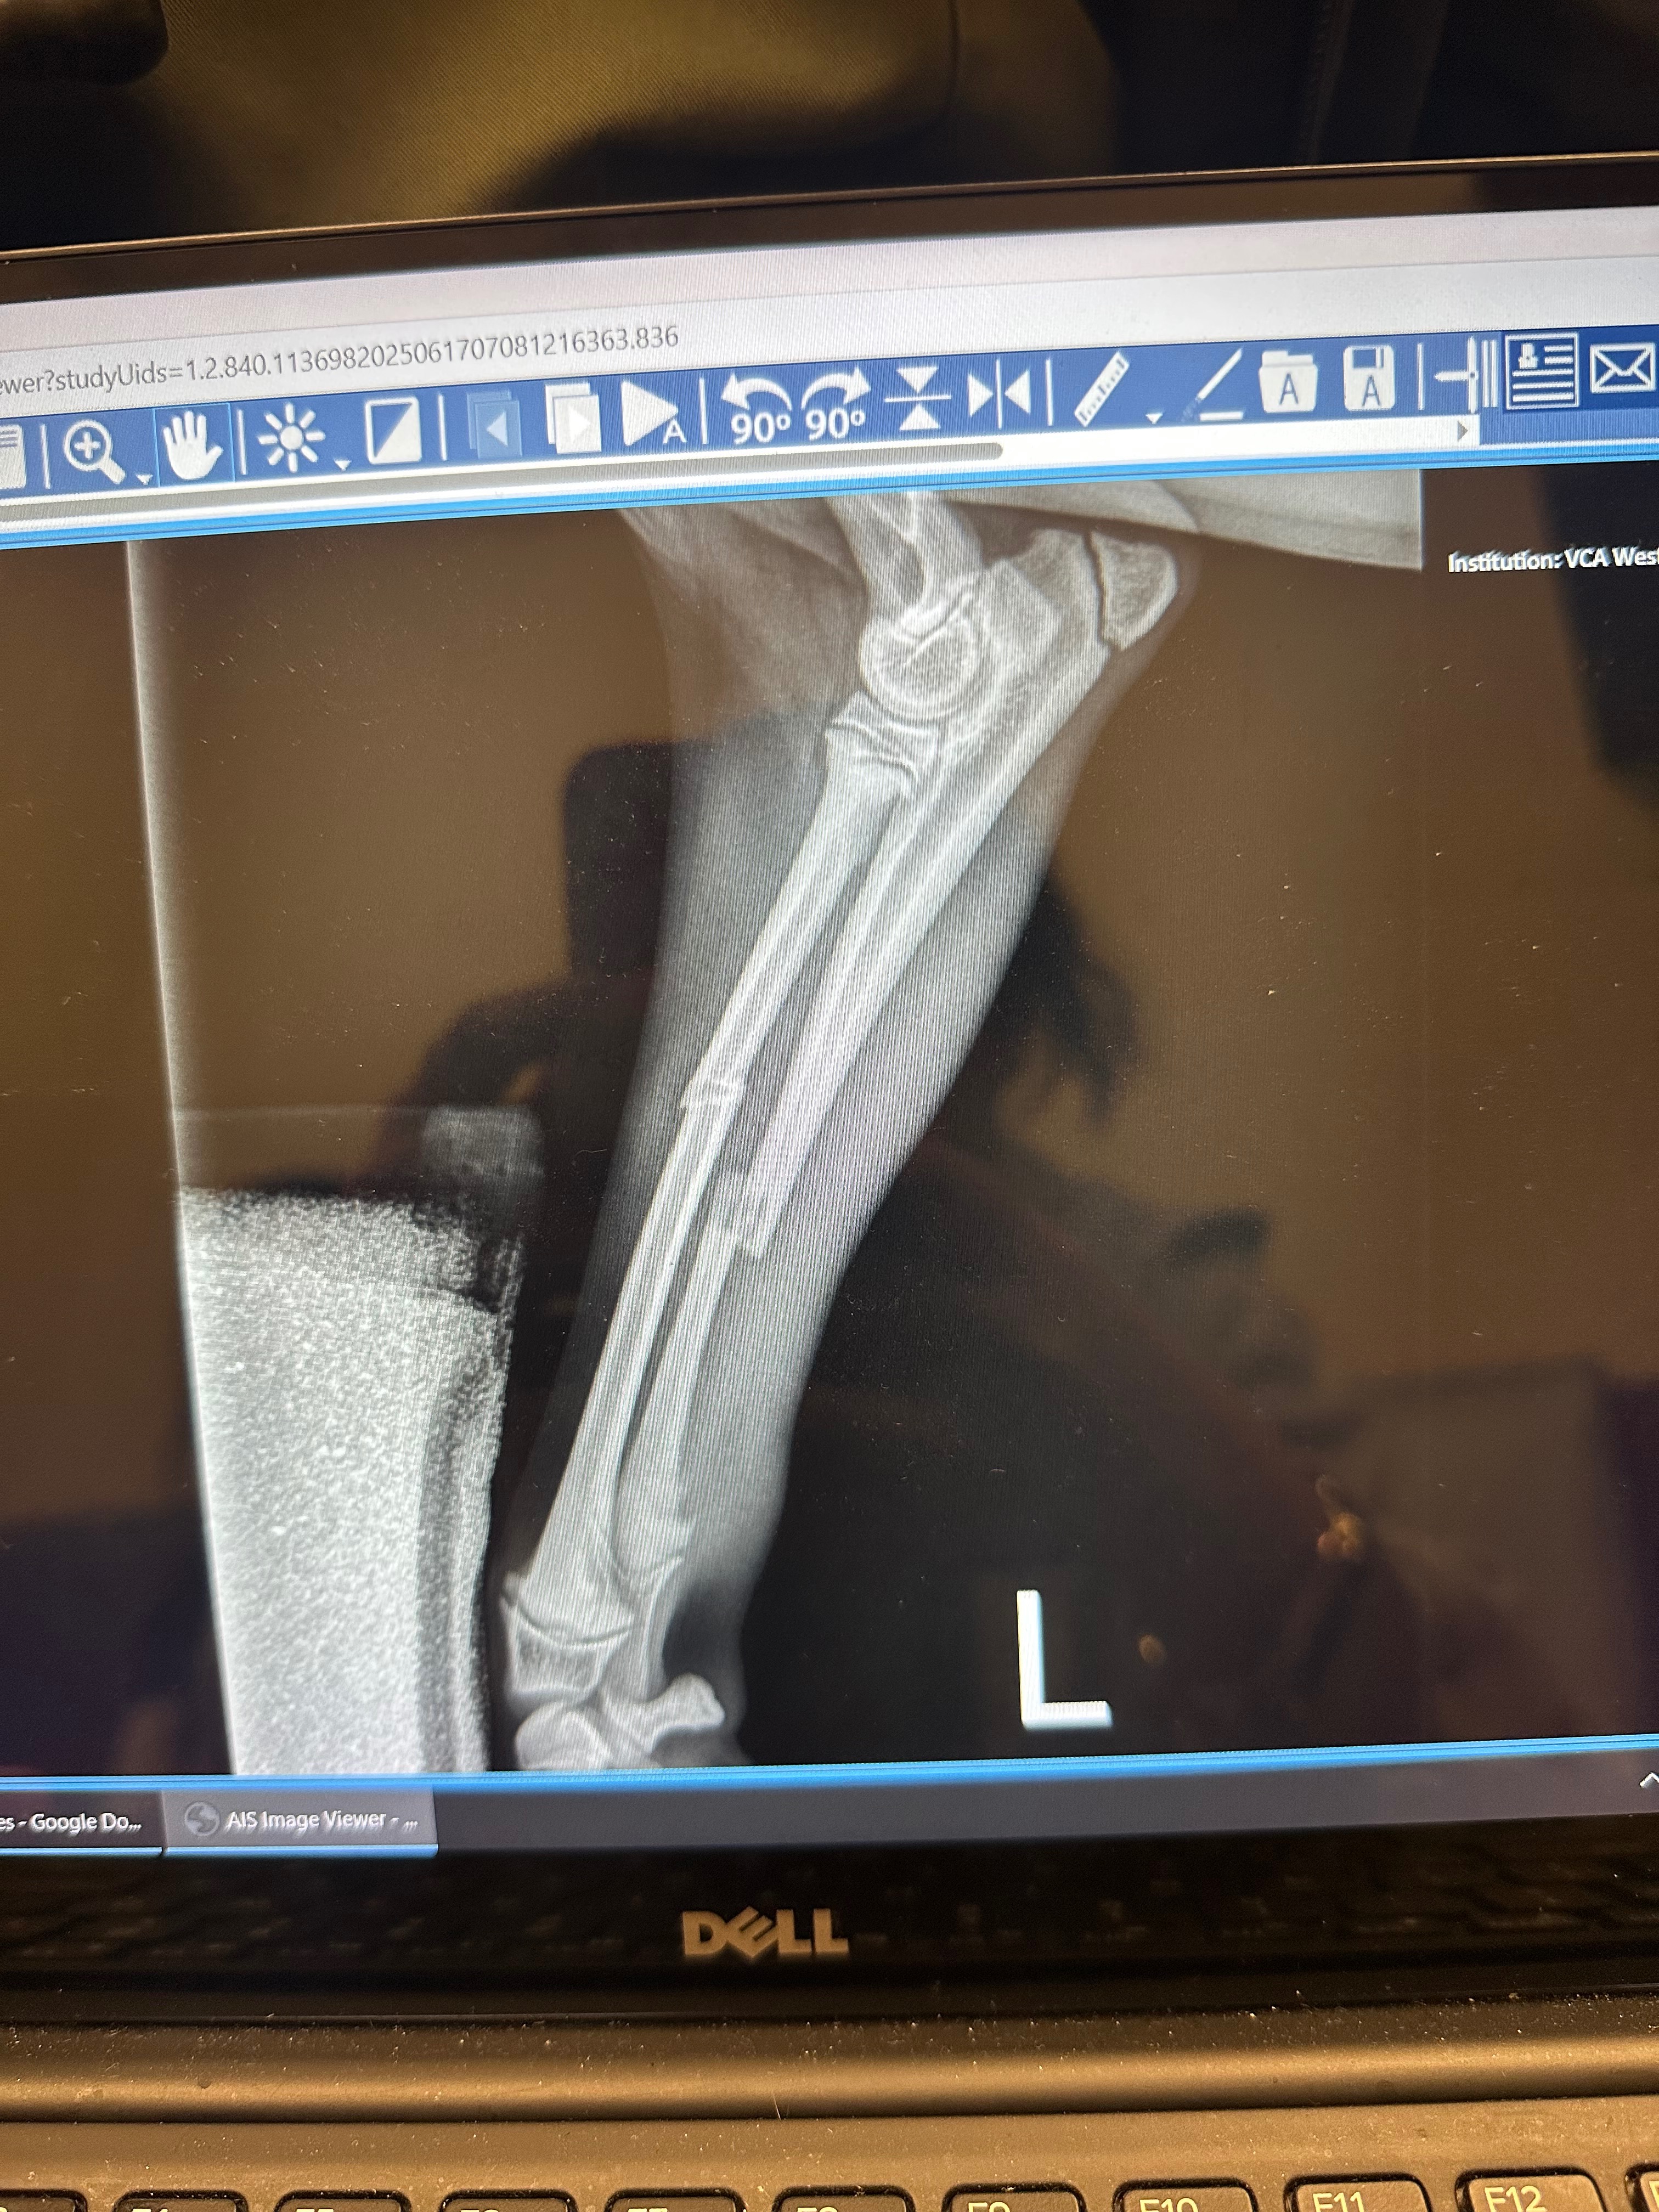

Our little Bo had a very bad accident last night when he jumped off the couch. His front, left leg snapped when he hit the ground and 2 of his bones broke. We rushed him to the emergency vet and were told that he unfortunately was going to need orthopedic surgery to fix his leg as soon as possible. Our family was unfortunately not prepared for the cost of this surgical procedure and hospital visits we have to keep making until he fully recovers.